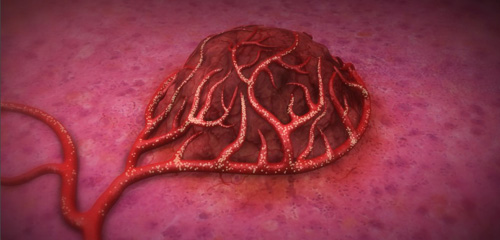

On the treatment day, you return back to Albany Medical Center. The day begins in our recovery room followed again the procedure performed in one of our interventional angiography suites. This time, however, we already have a plan in mind. We are able to place a catheter directly into the exact blood vessel supplying the tumor. Instead of injecting a radiotracer, we inject the Y90 this time. You will see people from our Radiation Safety office monitoring the injection as it is delivered. When the Y90 beads are injected, they eventually lodge within the tiny blood vessels inside the tumor. Over the next 2-3 weeks, they deliver a small amount of radiation that travels only 2 mm away from the injected particles. This radiation is able to treat the tumor while preventing the typical side effects of systemic therapies. There are often two treatment days since we like to treat each half of the liver on separate days.

This pictures demonstrates the Y90 microspheres traveling into the blood vessels surrounding and bringing blood to a tumor (www.sirtex.com).